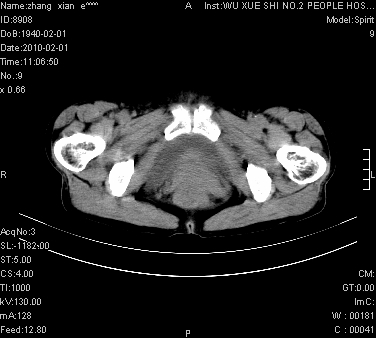

标题: CT24434:70岁 女 腹胀,腹水原因待查 [打印本页]

标题: CT24434:70岁 女 腹胀,腹水原因待查

大量腹水,脾脏囊性占位,子宫颈占位,右侧腹股沟淋巴结肿大,建议+c,先查妇科。

腹盆腔大量积液,子宫增大,子宫颈增大外形不规则,内见低密度影,膀胱后壁显示不清,右腹股沟肿大淋巴结,脾脏囊性占位,子宫颈占位,子宫颈癌?建议增强。

考虑:1、腹膜转移,大量腹水;

2、脾占位性病变;

3、左侧卵巢占位性病变,建议增强进一步检查。

考虑:1、腹膜转移,大量腹水;2、脾占位性病变;3、左侧卵巢占位性病变,建议增强进一步检查。支持